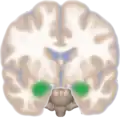

Location of the amygdalae in the human brain | |

Frontal and side view of amygdala

Frontal and side view of amygdala Amygdala along with other subcortical regions, in glass brain.

Amygdala along with other subcortical regions, in glass brain. Dorsal view of the amygdalae in an average human brain

Dorsal view of the amygdalae in an average human brain Frontal view of the amygdalae in an average human brain

Frontal view of the amygdalae in an average human brain Left lateral view of the amygdala in an average human brain

Left lateral view of the amygdala in an average human brain Amygdala highlighted in green on coronal T1 MRI images

Amygdala highlighted in green on coronal T1 MRI images Amygdala highlighted in green on sagittal T1 MRI images

Amygdala highlighted in green on sagittal T1 MRI images Amygdala highlighted in green on transversal T1 MRI images

Amygdala highlighted in green on transversal T1 MRI images